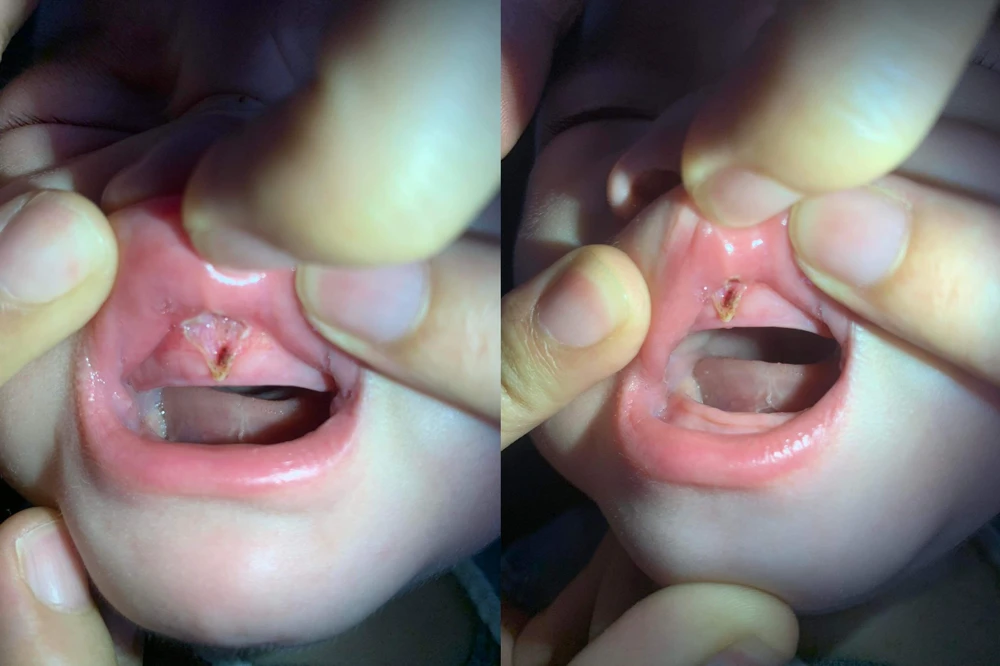

BS Sang cho hay, vừa có đồng nghiệp là BS chuyên khoa tai-mũi-họng chia sẻ về một ca bệnh nhi 6 tháng tuổi bị tổn thương sâu, đứt hãm môi và rách lợi do cắt thắng môi tại BS không phải chuyên khoa răng hay tai-mũi-họng nhi.

Trẻ bị tổn thương sâu, đứt hãm môi và rách lợi do cắt thắng môi. Ảnh: NVCC |

Cắt thắng môi, thắng lưỡi chỉ là tiểu phẫu, nguy cơ không nhiều, chủ yếu chảy máu khó cầm. Tuy nhiên nếu cắt quá sâu, cắt sai sẽ gây tổn thương sâu, đứt hãm môi và rách lợi.

“Khi trẻ không dính thắng môi thắng lưỡi, dính ít hoặc không được BS chuyên khoa chỉ định mà phụ huynh vẫn cho con đi cắt thì rất tội cho bé. Nếu không may trẻ bị tổn thương sau cắt, vết thương này sẽ đi theo trẻ suốt cuộc đời” - BS Sang bày tỏ.